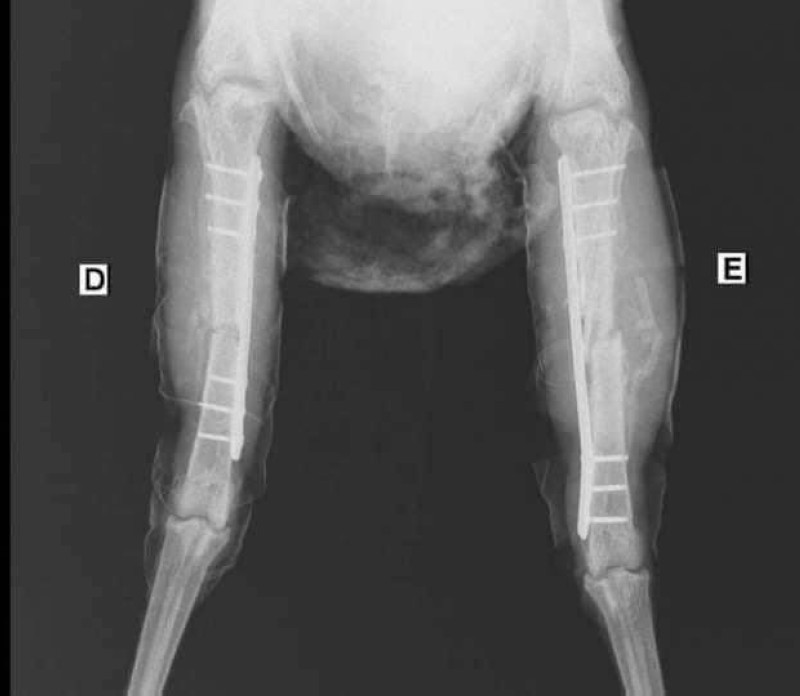

وأفادت وسائل إعلام مصرية بأن الدجاجة التي تسمى «ليسكي» تعرضت لكسر شديد في قدميها، وتطلب هذا الأمر عملية جراحية استغرقت نحو ساعتين، تم خلالها تركيب شريحتين و6 مسامير، بتكلفة وصلت إلى 7 آلاف جنيه (نحو 440 دولارا).

وتمت العملية الجراحية بعد خضوع الدجاجة للتعقيم، وبعض التحاليل الطبية، للتأكد من سلامة أعضائها الحيوية.

وقال الطبيب البيطري الذي أجرى العملية، محمد أحمد، إن العملية استغرقت نحو ساعة و45 دقيقة وشارك فيها طبيبان ومساعد آخر.